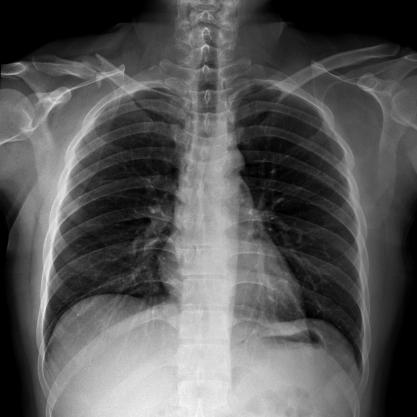

滿足不同身高的受檢者快速地進行胸片的靜態(tài)及動態(tài)檢查,適合大規(guī)模體檢。

SID可拉伸至1.8米,滿足標(biāo)準(zhǔn)胸片、職業(yè)性塵肺病檢查等特殊需求。